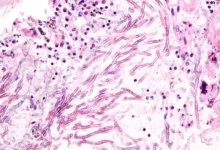

Вчені вперше випробували на людині препарат з вірусом, що вбиває ракові клітини

Експериментальний вірус, що вбиває рак, був вперше введений пацієнту-людині в надії, що…